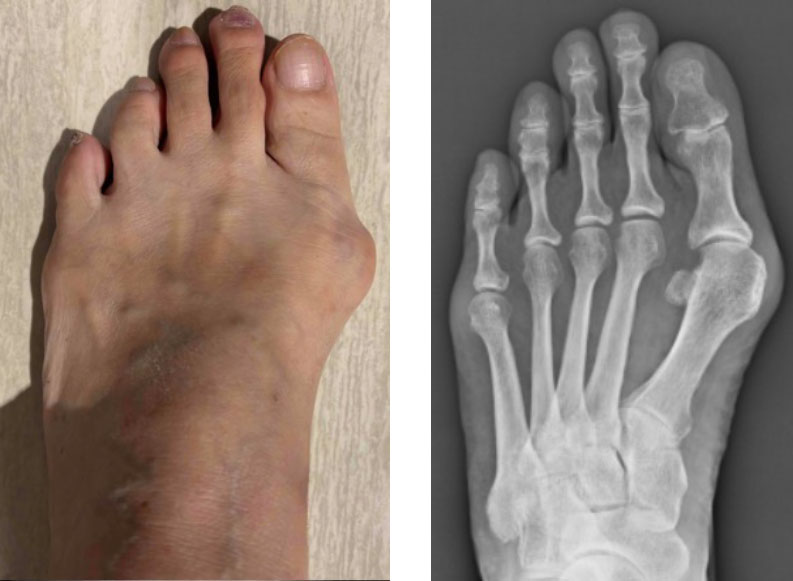

外反母趾

外反母趾とは、足の親指(母趾)がくの字に曲がり、付け根の関節が内側に突き出す変形のことです。男性にも見られますが、特に女性に多く、体重や足の形、靴の影響が大きいとされています。

・親指の付け根の出っ張り(内側への突出)

・靴に当たって赤くなって痛む

・親指が人差し指に重なるように曲がってくる